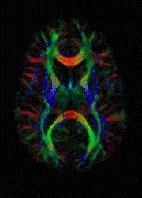

MRI de difusão

Mapeamento de cores DTI

MRI de difusão, IRM de difusão, ou imagem de difusão por ressonância magnética é um método IRM ou MRI (do inglês magnetic resonance imaging, obtenção de imagens por ressonância magnética) que produz imagens in vivo de tecidos biológicos ponderadas com as características microestruturais locais da difusão de água. O campo de MRI de difusão pode ser entendido em termos de duas classes distintas de aplicação—MRI ponderada de difusão e MRI de tensor de difusão. MRI ponderada de difusão pode prover informação sobre danos a partes do sistema nervoso. MRI de tensor de difusão pode prover informação sobre as conexões entre as regiões do cérebro.